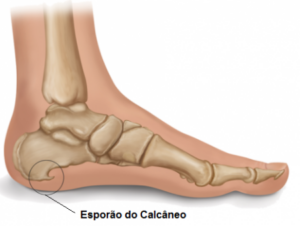

Sabe aquele esporão que insiste em aparecer no seu calcanhar? Pois é, ele é uma calcificação que surge no osso, bem na parte de baixo do calcâneo (o osso do seu calcanhar). Pensa nele como um pequeno “bico” de osso que se forma. Ele aparece justamente ali porque é um ponto de muita pressão e tensão na nossa pisada. A faixa de tecido que liga o calcanhar aos dedos, a fáscia plantar, sofre um estresse constante, e o corpo, na tentativa de proteger, cria essa estrutura óssea.

O esporão, basicamente, é um pequeno crescimento ósseo na parte de baixo do seu calcanhar. Quando a gente corre ou fica muito tempo em pé, essa área pode inflamar e causar aquela dor aguda. Os alongamentos ajudam a aliviar a pressão sobre o tendão e a fáscia plantar, que são os mais afetados.